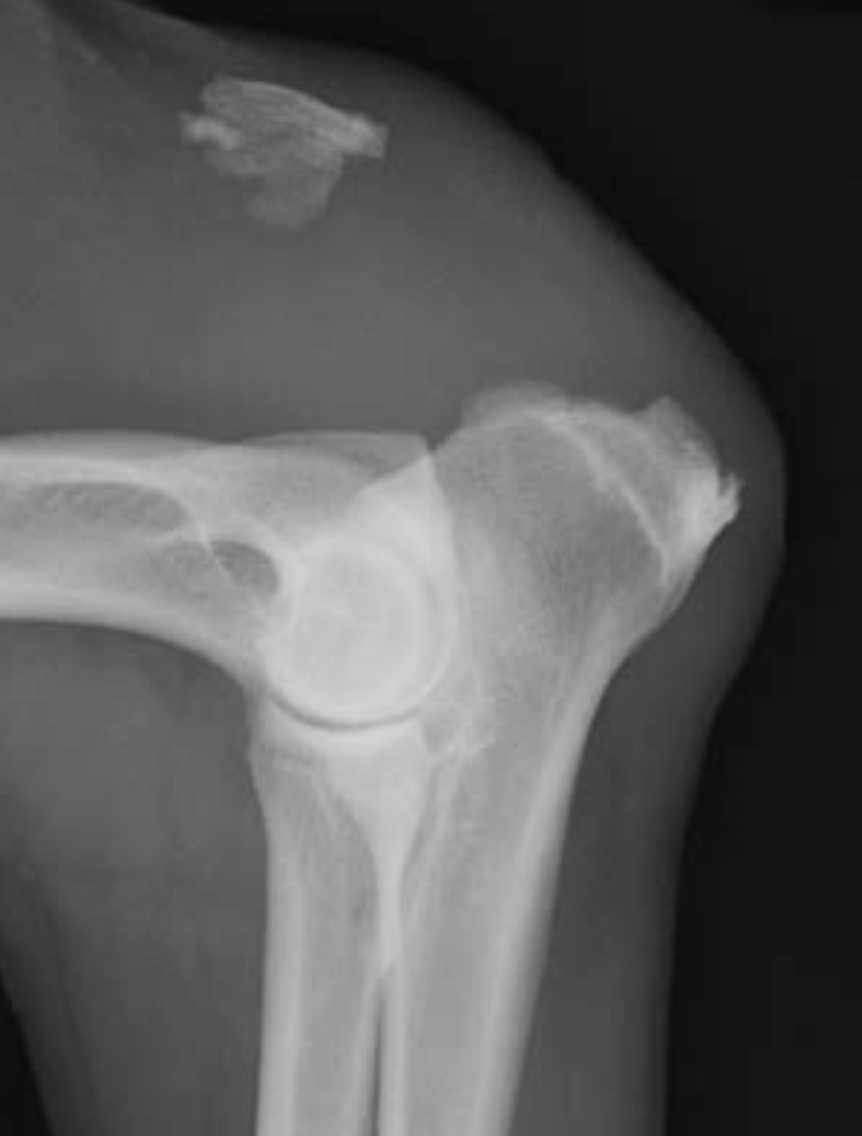

Point out: anconeal process, trochlear notch, medial and lateral coronoid process, medial and lateral epicondylar crest